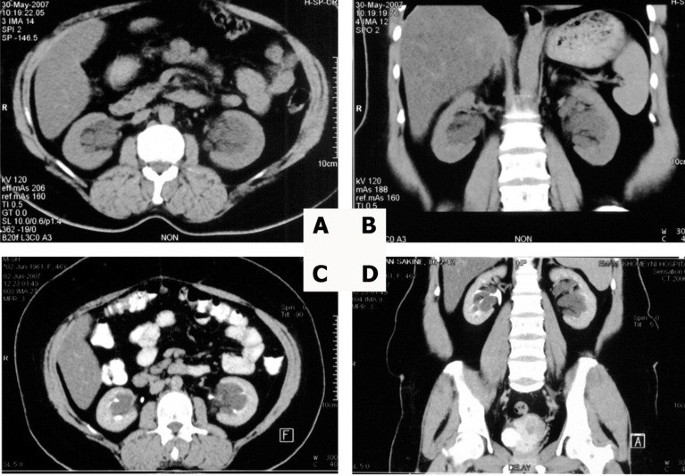

Pdf Bilateral Parapelvic Cysts That Mimic Hydronephrosis In Two Imaging Modalities A Case Report

Bilateral Parapelvic Cysts That Mimic Hydronephrosis In Two Imaging Modalities A Case Report Cases Journal Full

Pdf Bilateral Parapelvic Cyst Misdiagnosed As Hydronephrosis